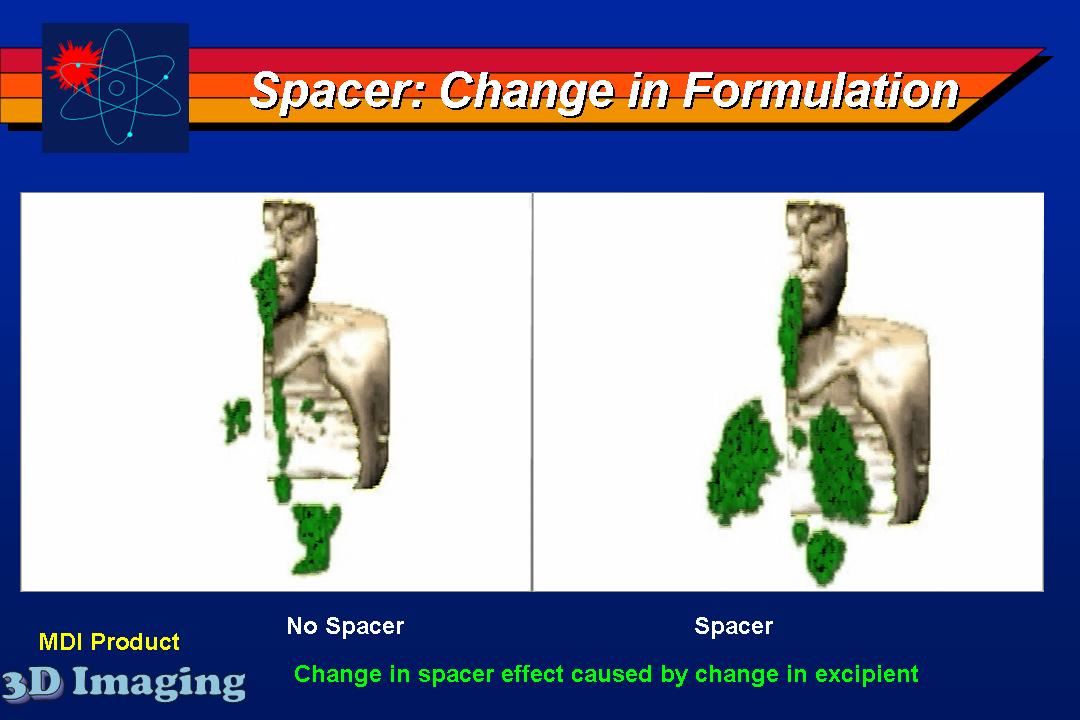

Several inhaled drug formulations were studied by radiolabeling the active ingredient (several different steriods) with C-11 or F-18, formulating that ingredient as the dosage form (different MDI, DPI, and nebulizer formulations), and performing quantitative PET studies of the regional biodistribution and kinetics.

Click on images to see additional examples, larger versions, and videos.